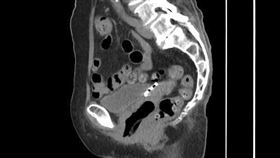

女腹痛求診 電腦斷層一照1物穿破子宮

嘉義一名6旬婦人因為下腹疼痛前往醫院就診,經檢查發現...

嚇!五旬婦腹痛不止 竟是避孕器穿透子宮

55歲的張女士日前因腹痛1個多月,本以為是腸胃症狀,...